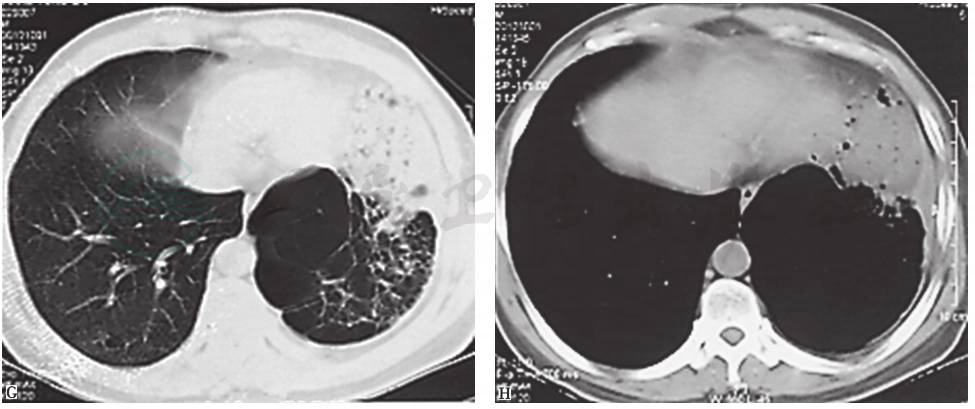

近13年来,患者胸部X线和CT均表现为左肺从初始体积大致正常,逐渐出现左肺体积减小,肺实质高密度影肺炎样改变;随着病情发展出现多发肺大疱、肺脓肿和肺毁损(图3~图10),并见左主支气管内病灶逐渐增大,最终导致管腔闭塞。

图4 10年半前胸部CT表现

胸部CT可见左主支气管被高密度钙化灶不全阻塞,左肺体积缩小,但透过度略有增高,同时伴左侧胸膜弥漫性增厚

引自:主编:.呼吸系统疑难病例诊疗辨析.第1版.ISBN:978-7-117-26415-0